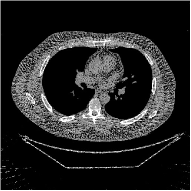

III-B3 Generalization Capability Comparisons between a “Denoising” Deep NN and the Proposed PWLS-ST- Method

This section compares the generalization capabilities between the proposed MBIR method, PWLS-ST-, and a denoising deep NN, FBPConvNet [14], that are trained from the phantom data; in particular, we tested the trained PWLS-ST- and FBPConvNet models to phantom and clinical scan data. The results in Fig. 6 show that the non-MBIR FBPConvNet method has higher overfitting risks, compared to the proposed PWLS-ST- MBIR method. When tested on clinical scan data, PWLS-ST- achieves much more accurate reconstruction, compared to FBPConvNet. See Fig. 6(b). When tested on phantom data, FBPConvNet generates more unnatural features as the number of views reduces, although it gives lower RMSE values compared to PWLS-ST-. See zoom-ins in Fig. 6(a). The FBPConvNet results above correspond to those in the recent work [16] that FBPConvNet [14] generated some unexpected structures.